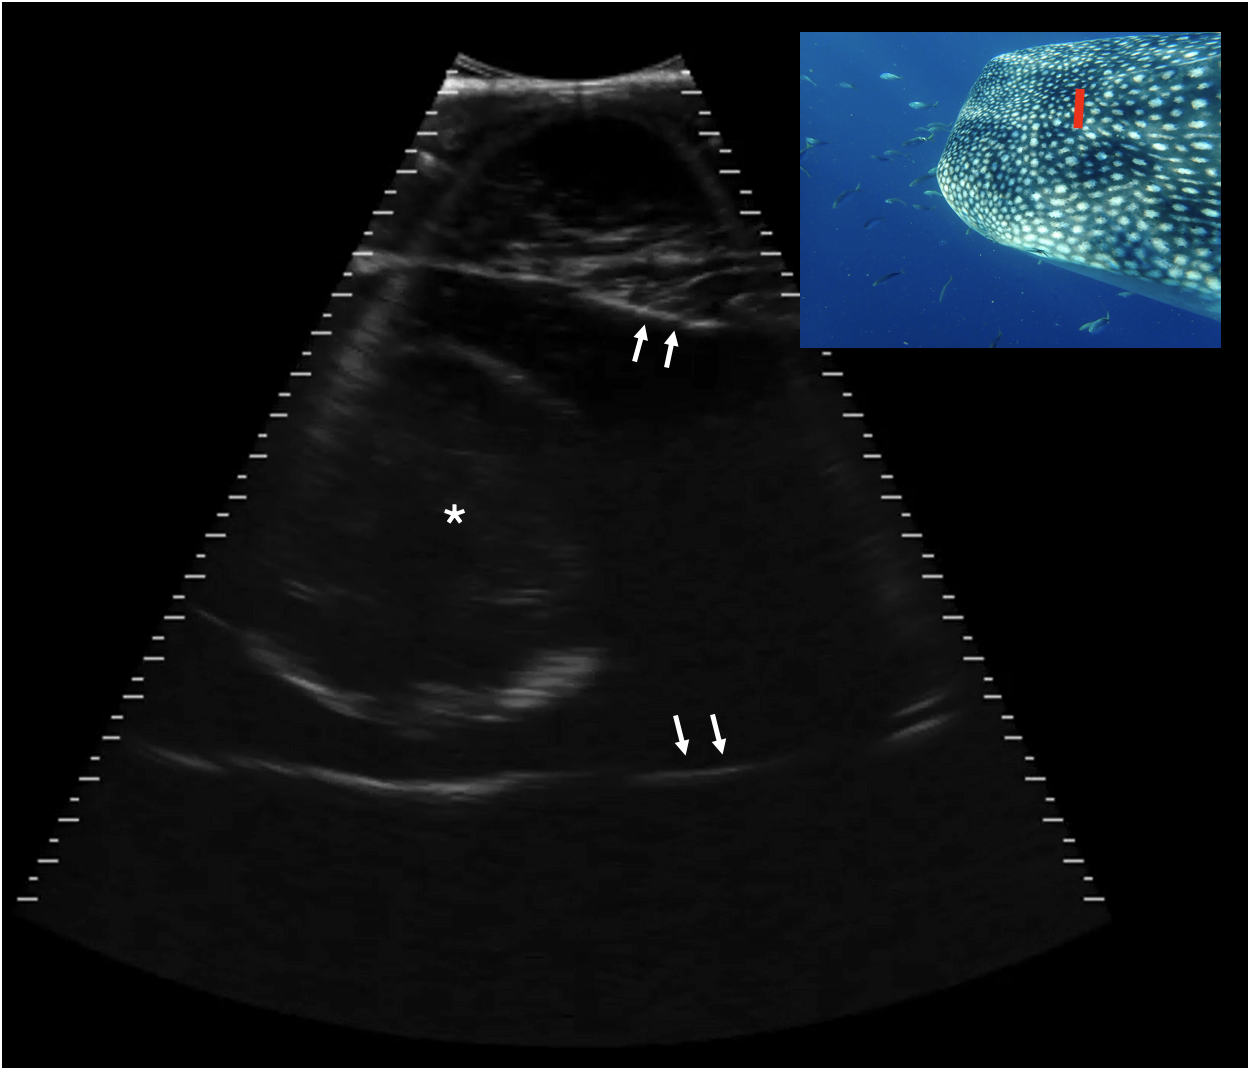

Figure 10

Transverse caudal neurocranium, slightly right of midline, Shark 78. The white arrows indicate the internal surface of the calvarial chamber, filled with anechoic fluid. Centrally in the chamber there is a circular structure 8.1 cm in height with a thin, hyperechoic (bright) capsule and some mixed internal echoes. This structure may represent the brain. Displayed depth 21 cm, left is to the right of the image. See video S8. Photograph insert shows dorsal view of a whale shark head and approximate transducer position in red. Photo credit Lucy Armstrong.